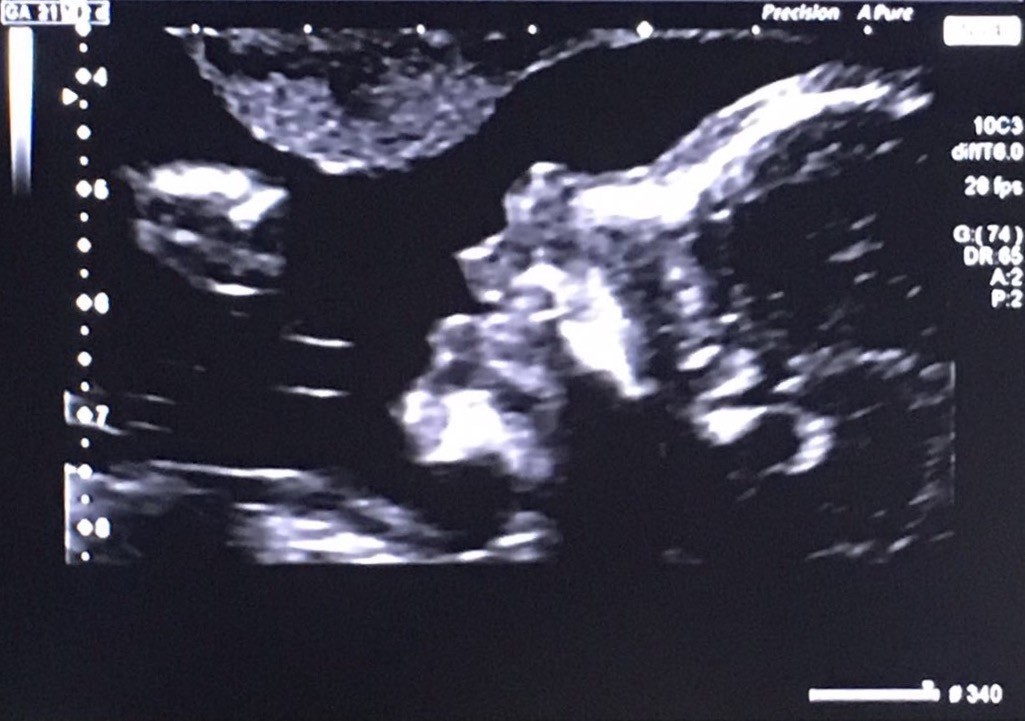

Alice, estamos à tua espera!

FullSizeRender-2.jpg

Já sei da tua existência desde o Natal mas obrigaram-me a um prolongado silêncio.

Porém, festejo-te há meses, e agora que sei que és uma menina e que já tens nome, festejo-te por inteiro, com outra intensidade, porque um nome, parecendo que não, já revela identidade, forma, peso, substância. Existência, enfim.

Querida sobrinha, cá te esperamos, com a alegria que sempre oferecemos a quem chega.

Parabéns, querida irfilha por mais esta felicidade. Parabéns querido cunhado. Parabéns, sobrinho João, por ires ser o mano mais velho. Ficaremos - também nós - mais próximos. Porque também eu sou mana mais velha. Une-nos, a partir de agora, mais essa circunstância tão boa da vida.